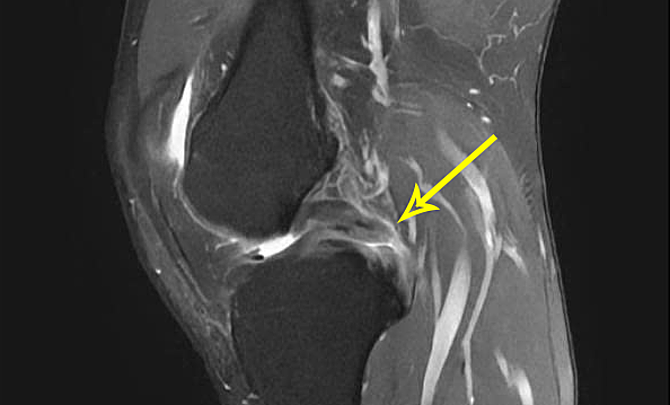

Bác sĩ Nghĩa phát hiện xương chày anh Giang tụt ra sau so với đùi, chỉ định chụp cộng hưởng từ MRI ghi nhận dây chằng chéo sau mất hoàn toàn tín hiệu. Bác sĩ chẩn đoán bệnh nhân đứt hoàn toàn dây chằng chéo sau độ ba.